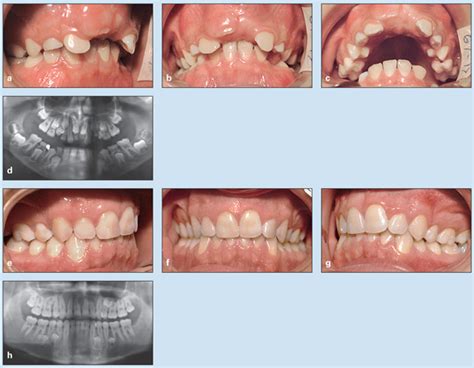

Hypodontia (Missing Teeth) People with hypodontia are born with missing teeth. Additionally, Hypodontia (congenitally missing teeth) can affect children's baby teeth and permanent teeth. Furthermore, This article delves into the causes, prevalence, clinical features, diagnostic approaches, and treatment options for hypodontia. Moreover, Hypodontia refers to the absence of one or more teeth. These findings regarding Hypodontia A Team Approach To Management provide comprehensive context for understanding this subject.

This article delves into the causes, prevalence, clinical features, diagnostic approaches, and treatment options for hypodontia

Apr 9, 2025 · What Is Hypodontia? Hypodontia is the most common dental anomaly that refers to the absence of 1 to 5 teeth. It results in the formation of gaps and spaces, which can result in the …